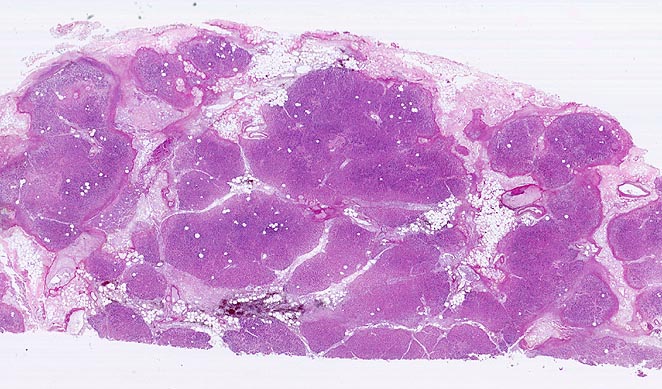

Basel 3BA HS/ Akute Pankreatitis (Kolliquationsnekrose)

Akute Pankreatitis (Kolliquationsnekrose)

Das Spektrum reicht von Ödem und Infiltraten neutrophiler Granulozyten ohne oder mit kleinen Fettgewebsnekrosen bei der interstitiell-ödematösen Variante über großflächige hämorrhagische Nekrosen im peripankreatischen Fettgewebe und im Pankreasparenchym bei der nekrotisch-hämorrhagischen Variante (Kurspräparat). Das peripankreatische Fettgewebe wird bei der nekrotisch-hämorrhagischen Variante durchsetzt von grösseren Fettgewebsnekrosen mit Verseifung, die gesäumt werden von dichten Infiltraten neutrophiler Granulozyten teils mit Abszessbildung. Die Hämorrhagien kommen durch Wandnekrosen kleiner und mittelgrosser Venen im peripankreatischen Fettgewebe zustande.

• Unregelmässige Nekrosestrassen durchziehen Fettgewebe und Pankreasparenchym.

• Die Grenzen zwischen vitalem und nekrotischem Gewebe sind unscharf.

• Frische, teils hämorrhagische autodigestive Kolliquationsnekrosen von Pankreasparenchym und Fettgewebe demarkiert von zerfallenden neutrophilen Granulozyten.

• Innerhalb der Nekroseareale Ablagerungen von amorphem gelborangem Hämatoidin (eisenfreies extrazelluläres Hämoglobinabbauprodukt).

• Nachweis kokkoider und fadenförmiger Bakterien im nekrotischen Fettgewebe. Das sollte der Kliniker dem Pathologen mitteilen: